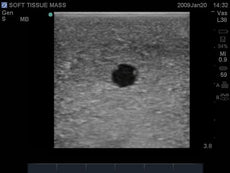

These bone-fracture training blocks help learners develop and practice the psychomotor skills necessary to gain ultrasound proficiency, including using ultrasound system controls, positioning and moving the transducer, recognizing bone fractures and manipulating fractured bones to identify normal versus abnormal imaging characteristics. Choose from two options: Greenstick Fracture, or Crepitus Fracture.

RESPECTIVE ANATOMY:Crepitus Bone Fracture

Greenstick Bone Fracture